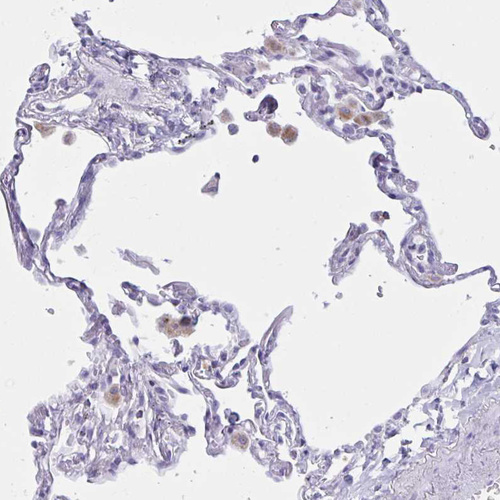

Immunohistochemical staining of human lung shows moderate cytoplasmic and secreted positivity in macrophages.